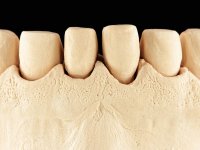

Realizado o diagnóstico e tomada a decisão quanto ao tratamento a executar, tornou-se importante definir qual a sequência de trabalho a adotar no sentido de conseguir a reabilitação da D.V.O. (V.D.O), de forma progressiva e equilibrada. Na primeira fase fez-se uma pré-impressão da arcada inferior com silicone tipo “putty” e em seguida realizou-se o preparo dentário de todo o sector posterior. O preparo para os overlays foi feito coronalmente à linha amelo cementaria no sentido de ser o mais conservador possível. A impressão foi feita com técnica de dupla mistura após afastamento gengival realizado com pasta de caulino. A provisória foi realizada com resina composta de polimerização dual. Em laboratório foram realizados os overlays após se ter aberto ligeiramente (1,5mm) a D.V.O. nos modelos montados em articulador semi-ajustável. Simultaneamente o sector antero-inferior foi encerado no sentido de acompanhar este aumento da D.V.O. Também foi confecionada uma chave de silicone translucido para posterior confeção dos provisórios antero-inferiores. Em boca foi primeiro realizada a provisionalização dos dentes anteriores utilizando resina composta previamente aquecida após preparação das superfícies dentárias para a adesão. Foi colocado o dique de borracha para promover o isolamento absoluto e posteriormente foram colados os overlays. Em laboratório foi realizada nova chave de silicone para confecionar os provisórios antero-superiores. Seguidamente em boca foram preparados os seis dentes antero-superiores após colocação do fio de afastamento gengival. Feita a preparação adequada das superfícies dentárias foi realizada a impressão com técnica de dupla mistura e a respetiva provisória. Em laboratório foram confecionadas 6 facetas feldespáticas num modelo de trabalho tipo “Geller”. A provisória foi removida e as facetas foram coladas em boca utilizando um isolamento relativo competente. Esta opção foi tomada em virtude de uma prévia experiencia negativa com a colocação do dique de borracha na mandibula. Após a colagem dos laminados antero-superiores foram dadas 12 semanas para avaliar a adaptação do paciente à nova situação e então iniciar a confeção das facetas antero-inferiores. Após colocação do fio de afastamento gengival. foram feitos os preparos dentários adequados e em seguida foi feita a impressão. Também foi feita a preparação do dente 3.4 que, entretanto, tinha sofrido uma fratura do overlay. As facetas e a restauração do 3.4 foram realizadas num modelo de trabalho tipo “Geller”. Após remoção da provisória, as facetas foram coladas em boca, utilizando um isolamento relativo pelas razões apontadas anteriormente. Após colocação do trabalho o paciente foi reabilitado por outros colegas com um implante na zona do 2.6 e substituição da coroa aparafusada sobre o implante colocado no local do 3.5. Posteriormente surgiram fraturas nos overlays dos dentes 4.7 e 3.7 que foram reabilitados com overlays em Zr.